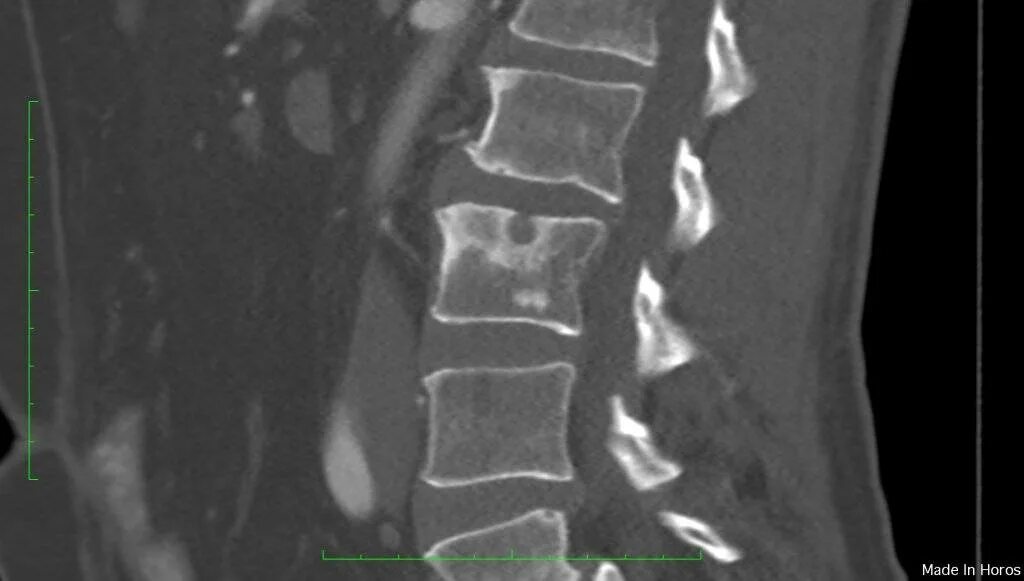

Что такое шморля в позвоночнике поясничном отделе